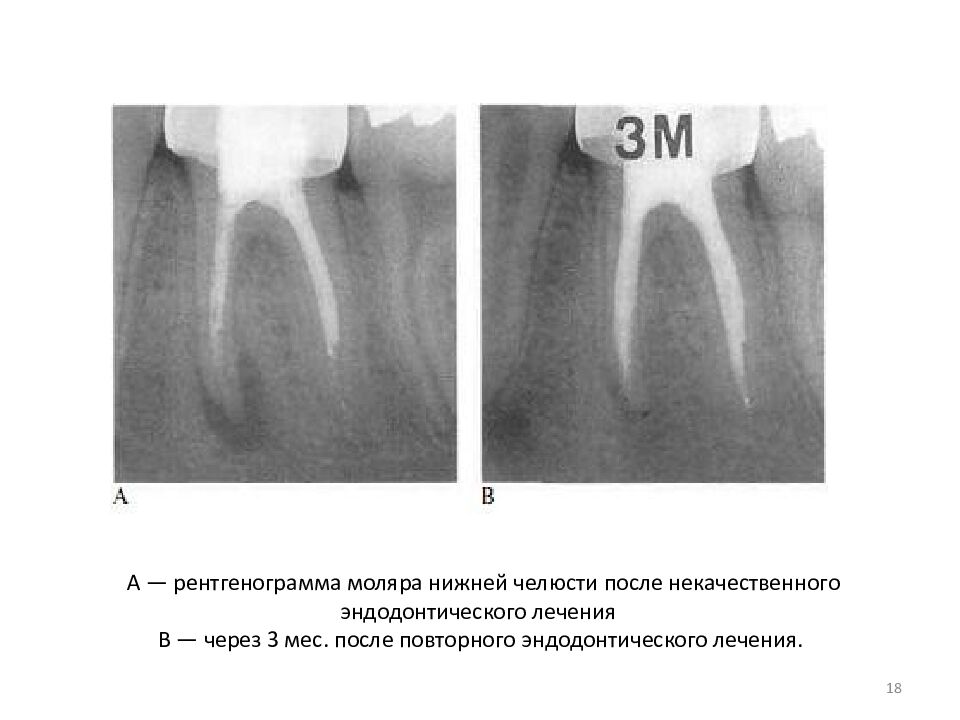

• А — рентгенограмма моляра нижней челюсти после некачественного эндодонтического лечения В — через 3 мес. после повторного эндодонтического лечения.